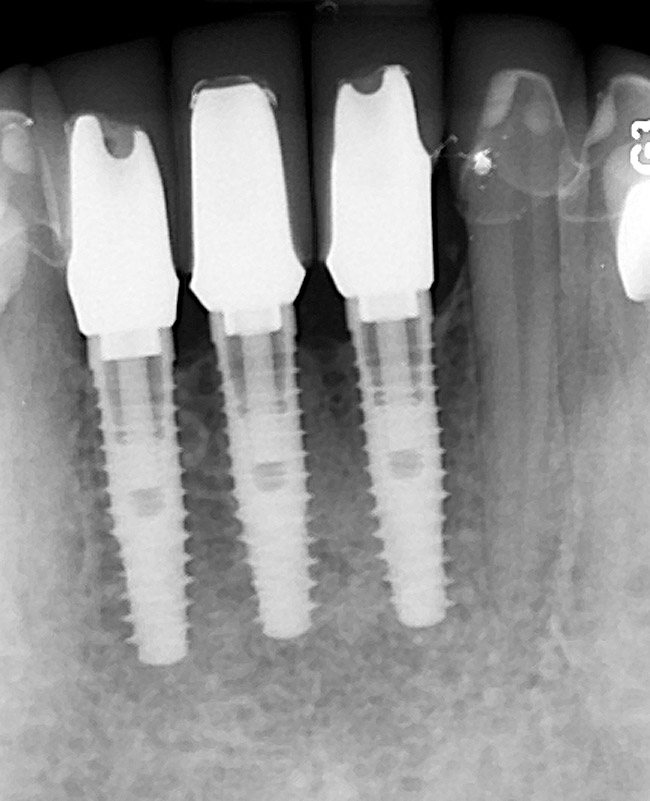

Figure 15  Regular-platform 4.3-mm x 16-mm implant positioned in osteotomy—periapical view.

Figure 15

The periodontist positioned a 4.3-mm x 16-mm regular-platform implant flush with the facial crest and 1 mm subcrestally interproximally (Figure 15), with a manually driven final seating torque value > 50 Ncm, followed by hand-tightened attachment of the immediate temporary abutment.